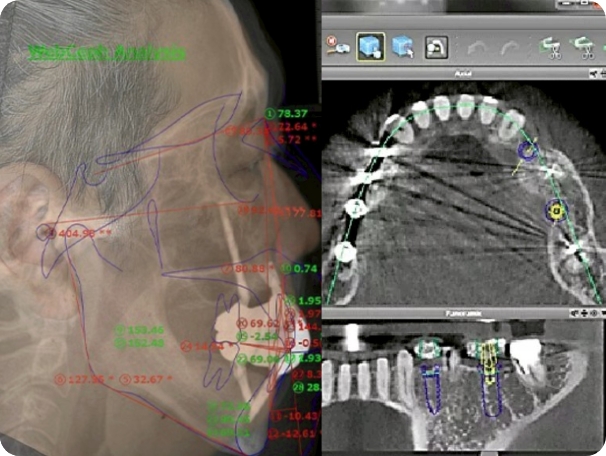

CT・模型データをもとに、CADでのデザインからジルコニア加工・ステイニングまで一貫して対応。歯科医師や歯科衛生士と連携しながら、精密で審美性の高い補綴装置をつくります。

All-on-4などの術後プロビジョナル製作/顎骨模型の3Dプリント・スキャン・クロスマウント/最終補綴物のデザイン〜製作、仕上げ